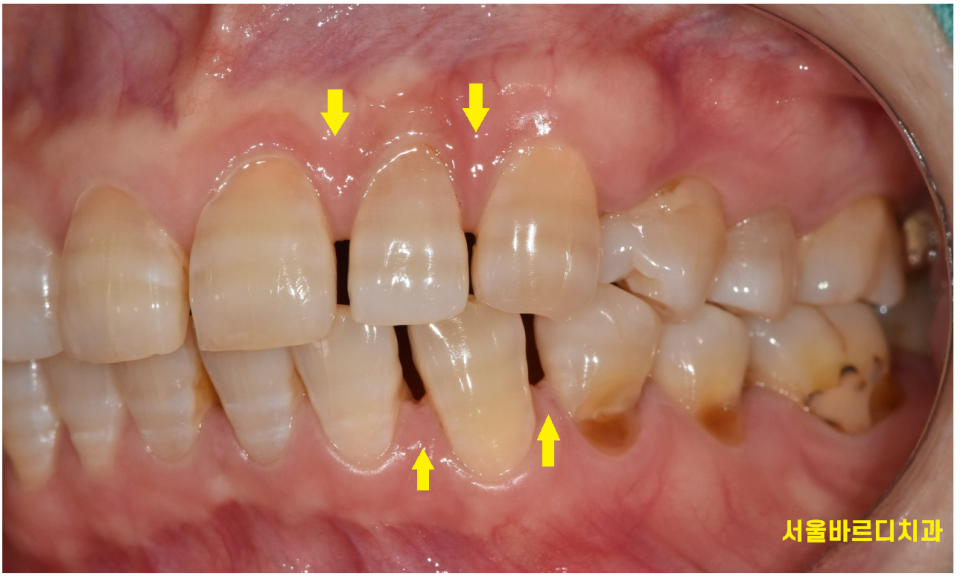

공간을 닫아주기 위해서는

몇개나 벌어졌는지?

벌어진 공간이 얼마나 큰지? 에 따라서

치료 방법이 결정됩니다!!

오늘 환자분은 앞니가 전반적으로 다 벌어지셨는데...

공간이 벌어지면 라미네이트를 하기에는 굉장히 유리한 조건입니다!

치아 삭제를 많이 하지 않아도...

라미네이트가 가능하거든요~~

돌출입을 해소하기 위해서라던가

치아 크기를 줄여주는 것이 아닌

라미네이트로 공간을 메꿔주면 되는 일이니까요!!